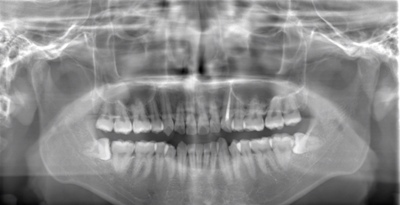

CASE 1

| 年齢・性別 | 30代・女性 |

| 主訴 | 左右に分けて親知らずを抜きたい、できれば痛くなく抜きたい |

| 親知らずのはえ方 | 完全に出ていてまっすぐはえている |

| 抜歯期間 | 15分 |

| 抜歯費用 | 約2,000円(保険内) |

| 抜歯内容 |

何度か虫歯になり痛みはないが早めに抜きたい。 完全に頭が出ているため歯ぐきを切ったり骨を削らずに抜歯しました。 根の形も単純なため抜歯自体は5分もかからず上下ともに終わりました。 術後痛みや腫れも出ていません。 抜歯後は感染をしやすいため必ず抗生物質を飲み切ってください。 |